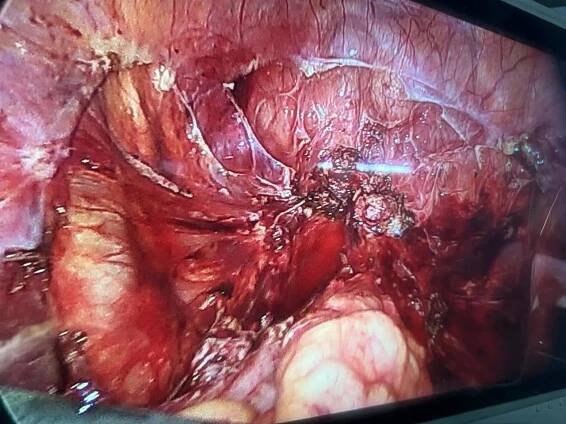

Endometriosis FAQ - Facts, Diagnosis, Treatment, India

gynaecologistkolkata.org